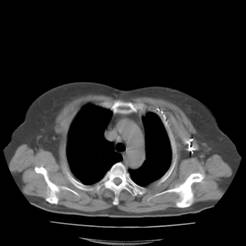

典型病例1:患者鞠xx,女,68岁,住院号:488141,因左胸痛1月余入院。2015年3月31日胸部增强CT示:左肺下叶2.5cmx2.8cm占位,左侧第三前肋骨溶骨性转移、形成厚约3cm肿块,左侧腋窝淋巴结2.1cmx4.1cm及前纵膈淋巴结转移。患者于2015年4月1日经CT引导下穿刺活检、病理证实为左肺下叶腺癌。于2015年4月5日对其采用125I放射性粒子置入治疗。治疗3个月随访,患者胸痛缓解,左肺下叶原发病灶消失,粒子聚集;左侧第三前肋骨基本恢复正常形态;前纵膈淋巴结消失,粒子聚集;左侧腋窝淋巴结缩小2/3。目前患者生活质量良好,可从事一般家务劳动。

术后三个月CT片: